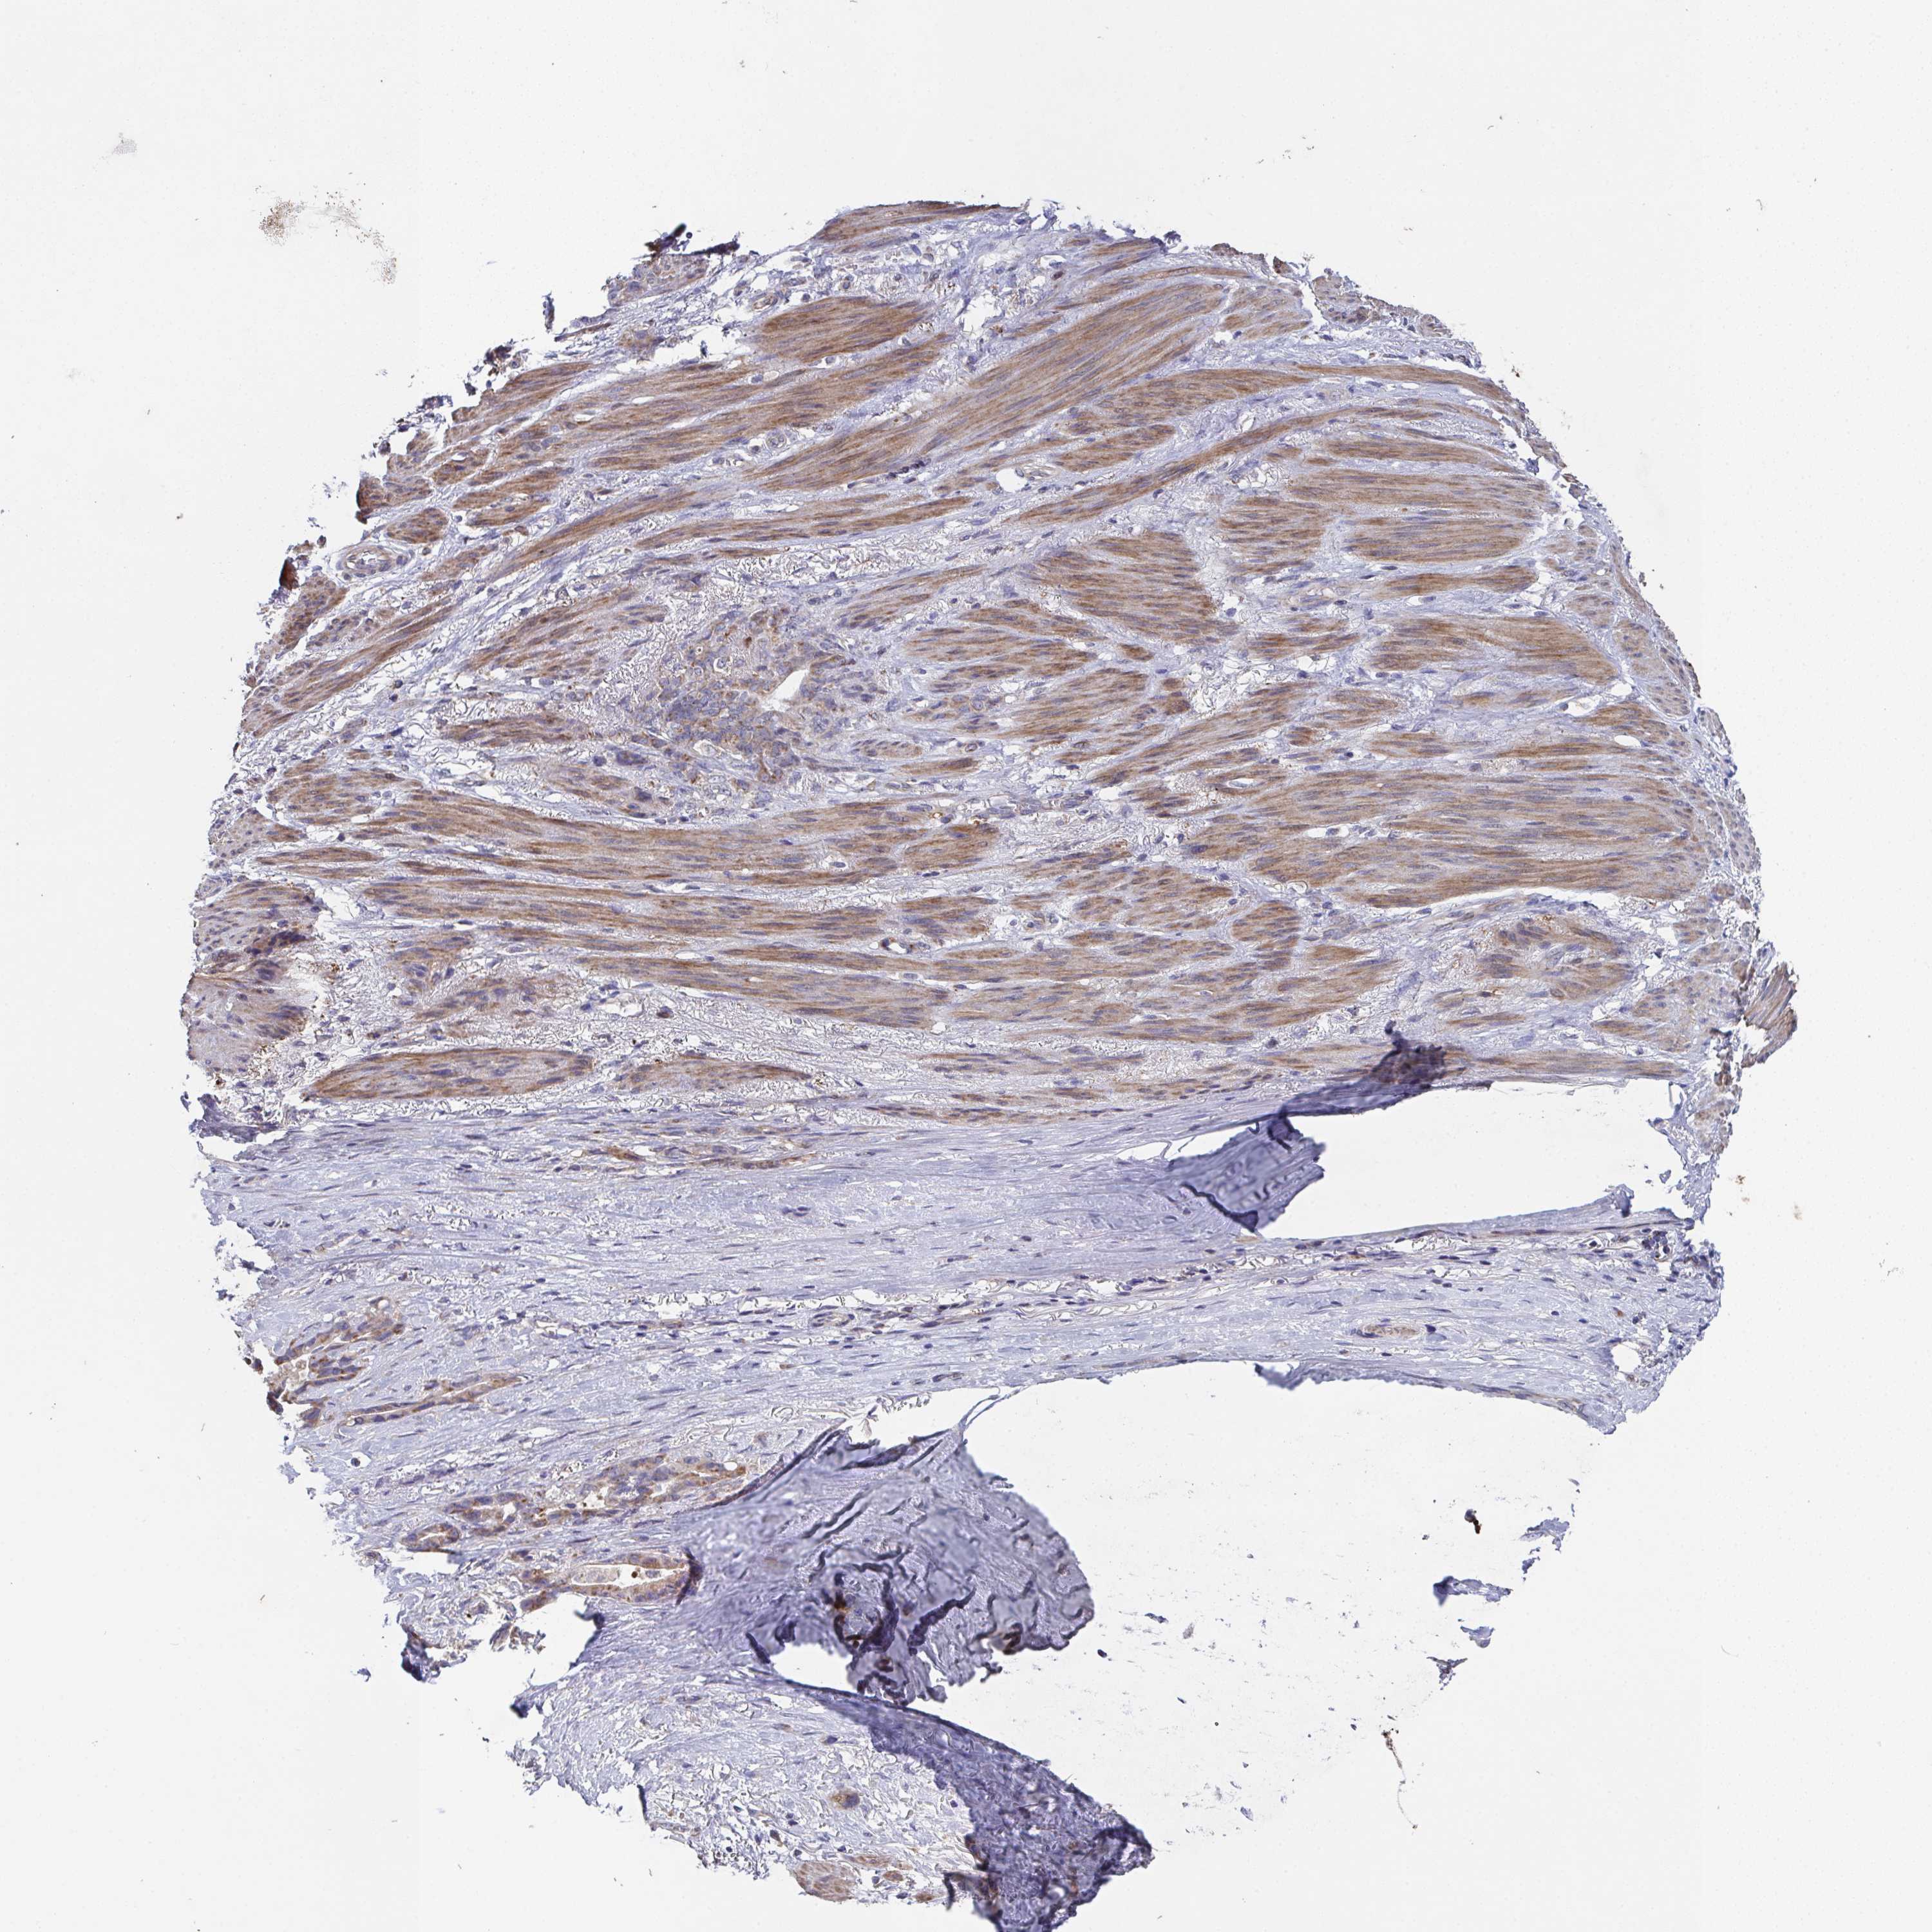

STOMACH CANCER - Protein expressioni

A mouse-over function shows sample information and annotation data. Click on an image to view it in a full screen mode. Samples can be filtered based on level of antibody staining by selecting one or several of the following categories: high, medium, low and not detected. The assay and annotation is described here.

Note that samples used for immunohistochemistry by the Human Protein Atlas do not correspond to samples in the TCGA dataset.

Antibody stainingi

Antibody staining in the annotated cell types in the current human tissue is reported as not detected, low, medium, or high, based on conventional immunohistochemistry profiling in selected tissues. This score is based on the combination of the staining intensity and fraction of stained cells.

Each image is clickable and will lead to virtual microscopy that enables deeper exploration of all samples and also displays staining intensity scores, fraction scores and subcellular localization as well as patient and tissue information for each sample.

Antibody HPA063296

Staining

High

Medium

Low

Not detected

Intensity

Strong

Moderate

Weak

Negative

Quantity

>75%

75%-25%

<25%

None

Location

Nuclear

Cytoplasmic/membranous

Cytoplasmic/membranous,nuclear

Adenocarcinoma, NOS